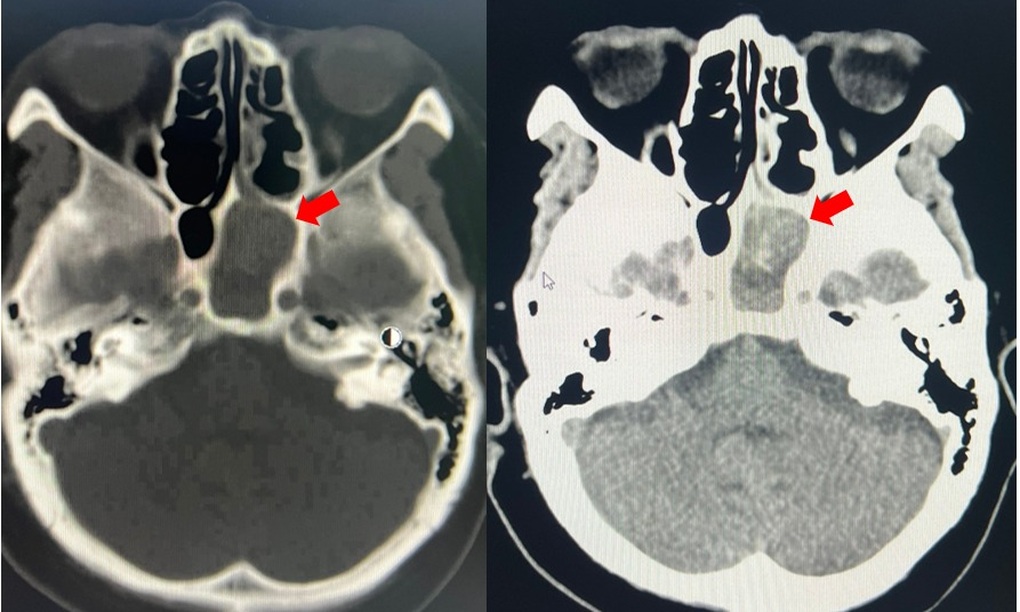

Bệnh nhân L.V.H. (sinh năm 2011, dân tộc Thái, ở Sơn La) được chuyển đến Bệnh viện Bệnh Nhiệt đới Trung ương trong tình trạng viêm xương đùi, áp xe cơ, viêm phổi, tràn dịch màng phổi và không đi lại được. Trước đó, cháu hoàn toàn khỏe mạnh.Theo lời kể của gia đình, trong thời gian ở nhà với ông bà do bố mẹ đi làm xa, H. bị lợn của gia đình cắn vào vùng đầu gối chân phải.Do chủ quan, vết thương không được làm sạch, gia đình cũng không đưa cháu đến cơ sở y tế để thăm khám.7 ngày sau, cháu bắt đầu...